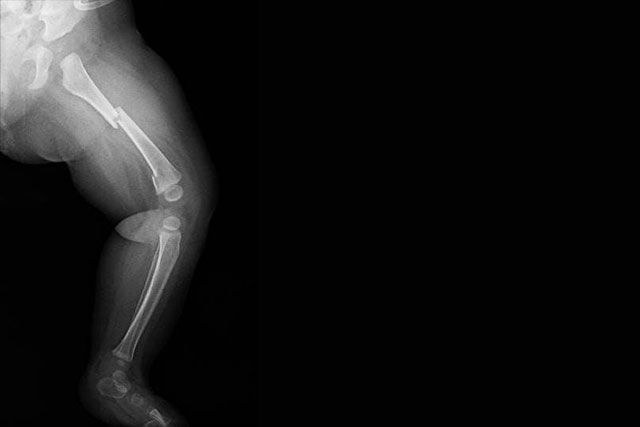

- Esguinces de tobillo y rodilla

- Lesiones de ligamentos cruzados y meniscos

- Fracturas por estrés o impacto

Se realiza un abordaje integral que incluye diagnóstico clínico y por imagen (rayos X, ultrasonido, resonancia), plan terapéutico individualizado y asesoría para el retorno seguro al deporte.